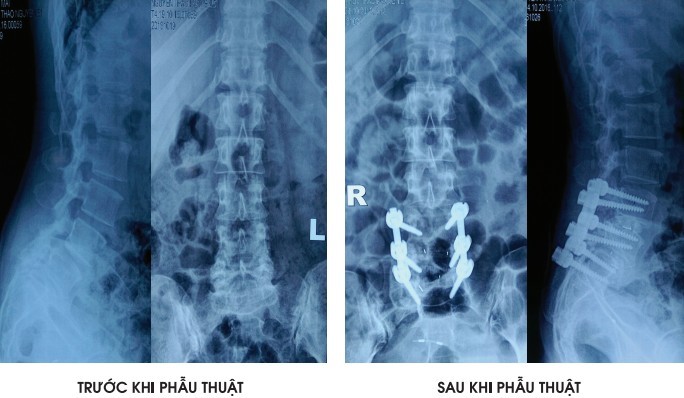

| Các đinh vít được định vị chính xác gần như tuyệt đối nhờ công nghệ mới |

Theo BS Du, trong phẫu thuật cột sốt, chỉ sai số 1mm đã có thể khiến chiếc ốc vít đi vào mạch máu và dây thần kinh, gây tai biến cho bệnh nhân. Trong đó nhẹ nhất là mất máu, nặng nhất là gây liệt.

Theo đó các bác sĩ khi tái tạo lại cấu trúc sinh lý cột sống bằng các vật liệu thay thế như nẹp, vít, ốc, đĩa đệm nhân tạo sẽ phải đảm bảo tủy sống, rễ thần kinh, mạch máu và các cấu trúc xương, dây chằng xung quanh không bị tổn thương.

Với công nghệ cũ C-arm, chỉ cho phép nhìn cột sống trên mặt phẳng một chiều nên bác sĩ phải tự tưởng tượng ra các chi tiết giải phẫu, bao gồm cả đường đi, kích thước của ốc vít với độ chính xác chỉ đạt 72-92%. Do đó bệnh nhân dễ gặp tai biến.

Mới đây, thế giới áp dụng kĩ thuật mới cho hình ảnh không gian 3 chiều O-arm kết hợp với hệ thống định vị giúp xác định vị trí giải phẫu gần 100%.